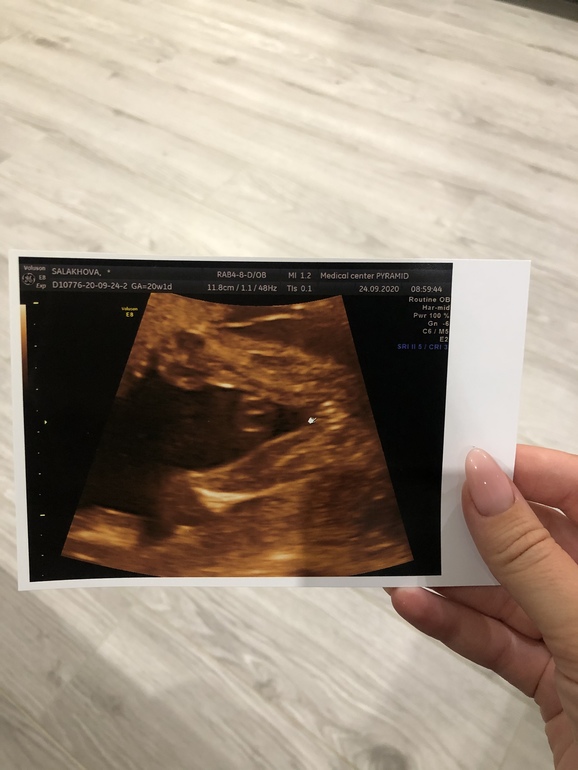

Сегодня ходили на 2 скрининг, маленько остаём от своего срока, до этого опережали, сейчас на пару дней остаем 😀 вес 281 гр, все органы развиты в срок и без Патологий. Такая она у нас стесняшка, ни в какую не даёт посмотреть на ее личико 🥰🎀 Муж так умилялся сегодня на узи, говорит моя кнопочка, копия моей любимой мармеладки(он меня так называет)😍 Он уверен, что она похожа будет на меня ♥️

И наш цветочек, Сомнений больше нет, что девочка у нас 🎀